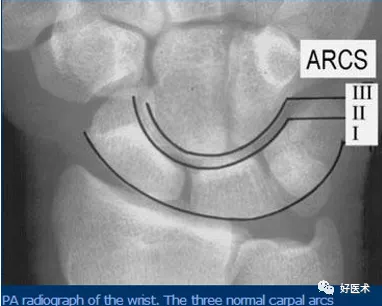

3.腕骨弧線

- 弧線Ⅰ為沿舟骨、月骨、三角骨近側凸面的光滑曲線。

- 弧線Ⅱ為其遠側凹面的光滑曲線。

- 弧線Ⅲ為頭狀骨和鉤骨近側的曲面。

腕骨弧線中斷

弧線中斷提示骨折或韌帶斷裂導致的半脫位或脫位。

上圖顯示弧線 Ⅰ 在月骨-三角骨關節處的中斷。

弧線 Ⅱ 中斷於舟月關節和月骨-三角骨關節(上圖)。弧線 Ⅰ 雖有缺口但仍呈光滑弧線,可認為是完整的。

弧線 Ⅲ 中斷,上圖顯示頭狀骨-鉤骨關節異常階梯狀改變。